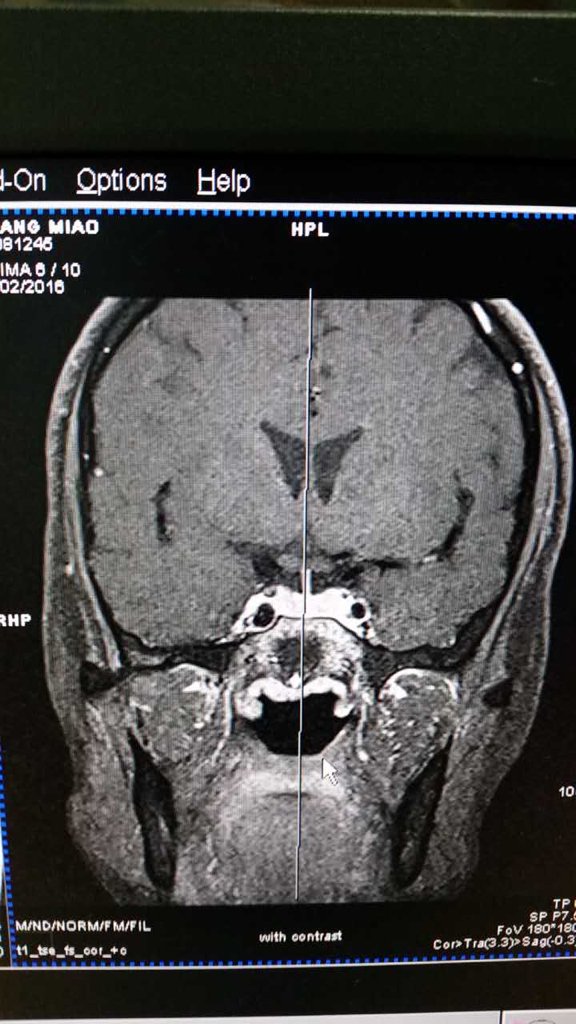

我28岁,未婚未育但因为月经不调,泌乳素200,于是做了垂体磁共振,麻烦懂的医生看看这片子里有没有

我28岁,未婚未育但因为月经不调,泌乳素200,于是做了垂体磁共振,麻烦懂的医生看看这片子里有没有瘤?或者异常?